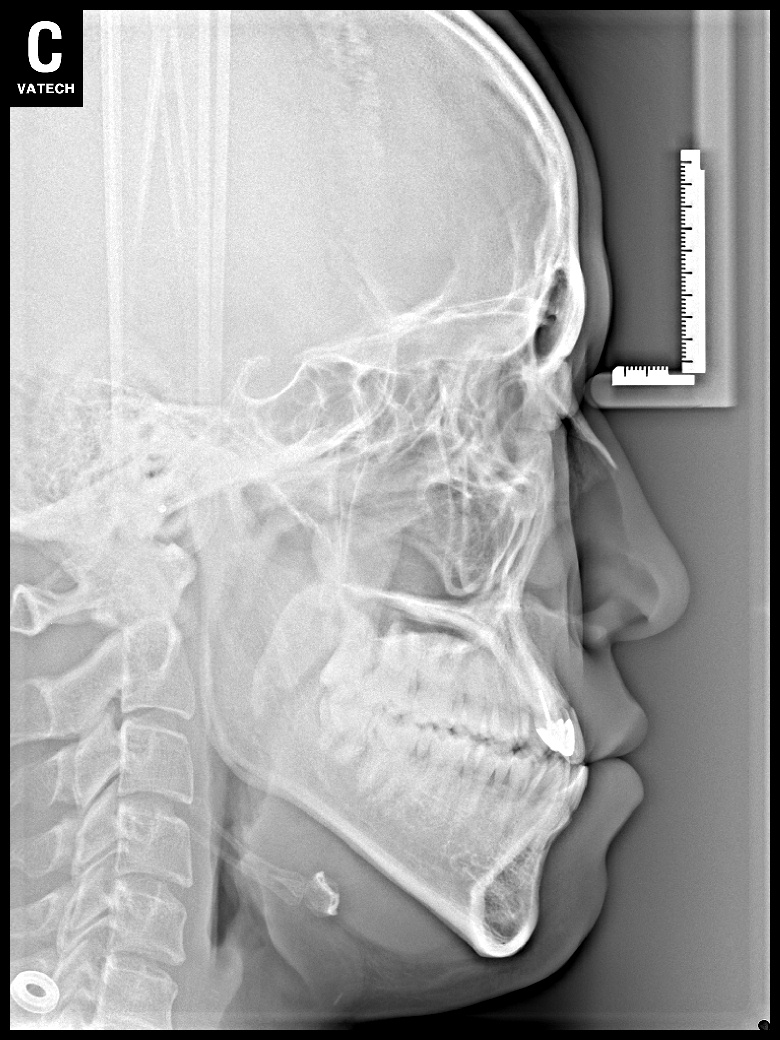

치료 후 사진입니다.